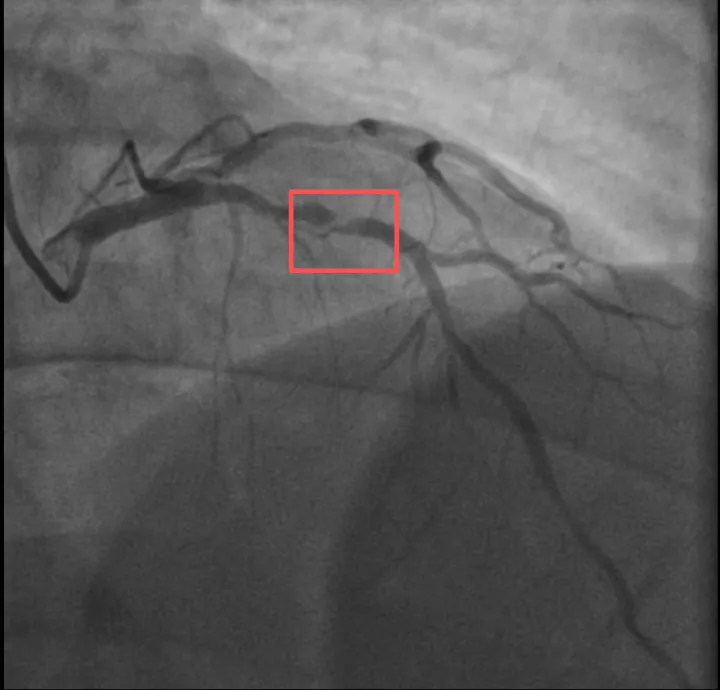

介入治疗前影像图

浙江医院心血管内科的医生分析,剧烈运动导致这位患者心脏的不稳定斑块破裂,进而造成前降支近段次全闭塞。所幸送医及时,孙先生的身体险情被化解。

介入治疗后影像图